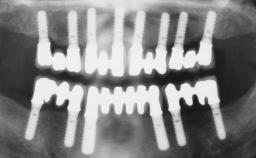

Immediate Loading of Six Implants in the Maxilla and Final Restoration with a Full-Arch CAD/CAM Zirconia FDP

# of Implants 6

Bone Augmentation Horizontal|Simultaneous

Defining Characteristics Fully edentulous upper jaw to be rehabilitated with four or more implants

Modality 6+ implants with immediate loading